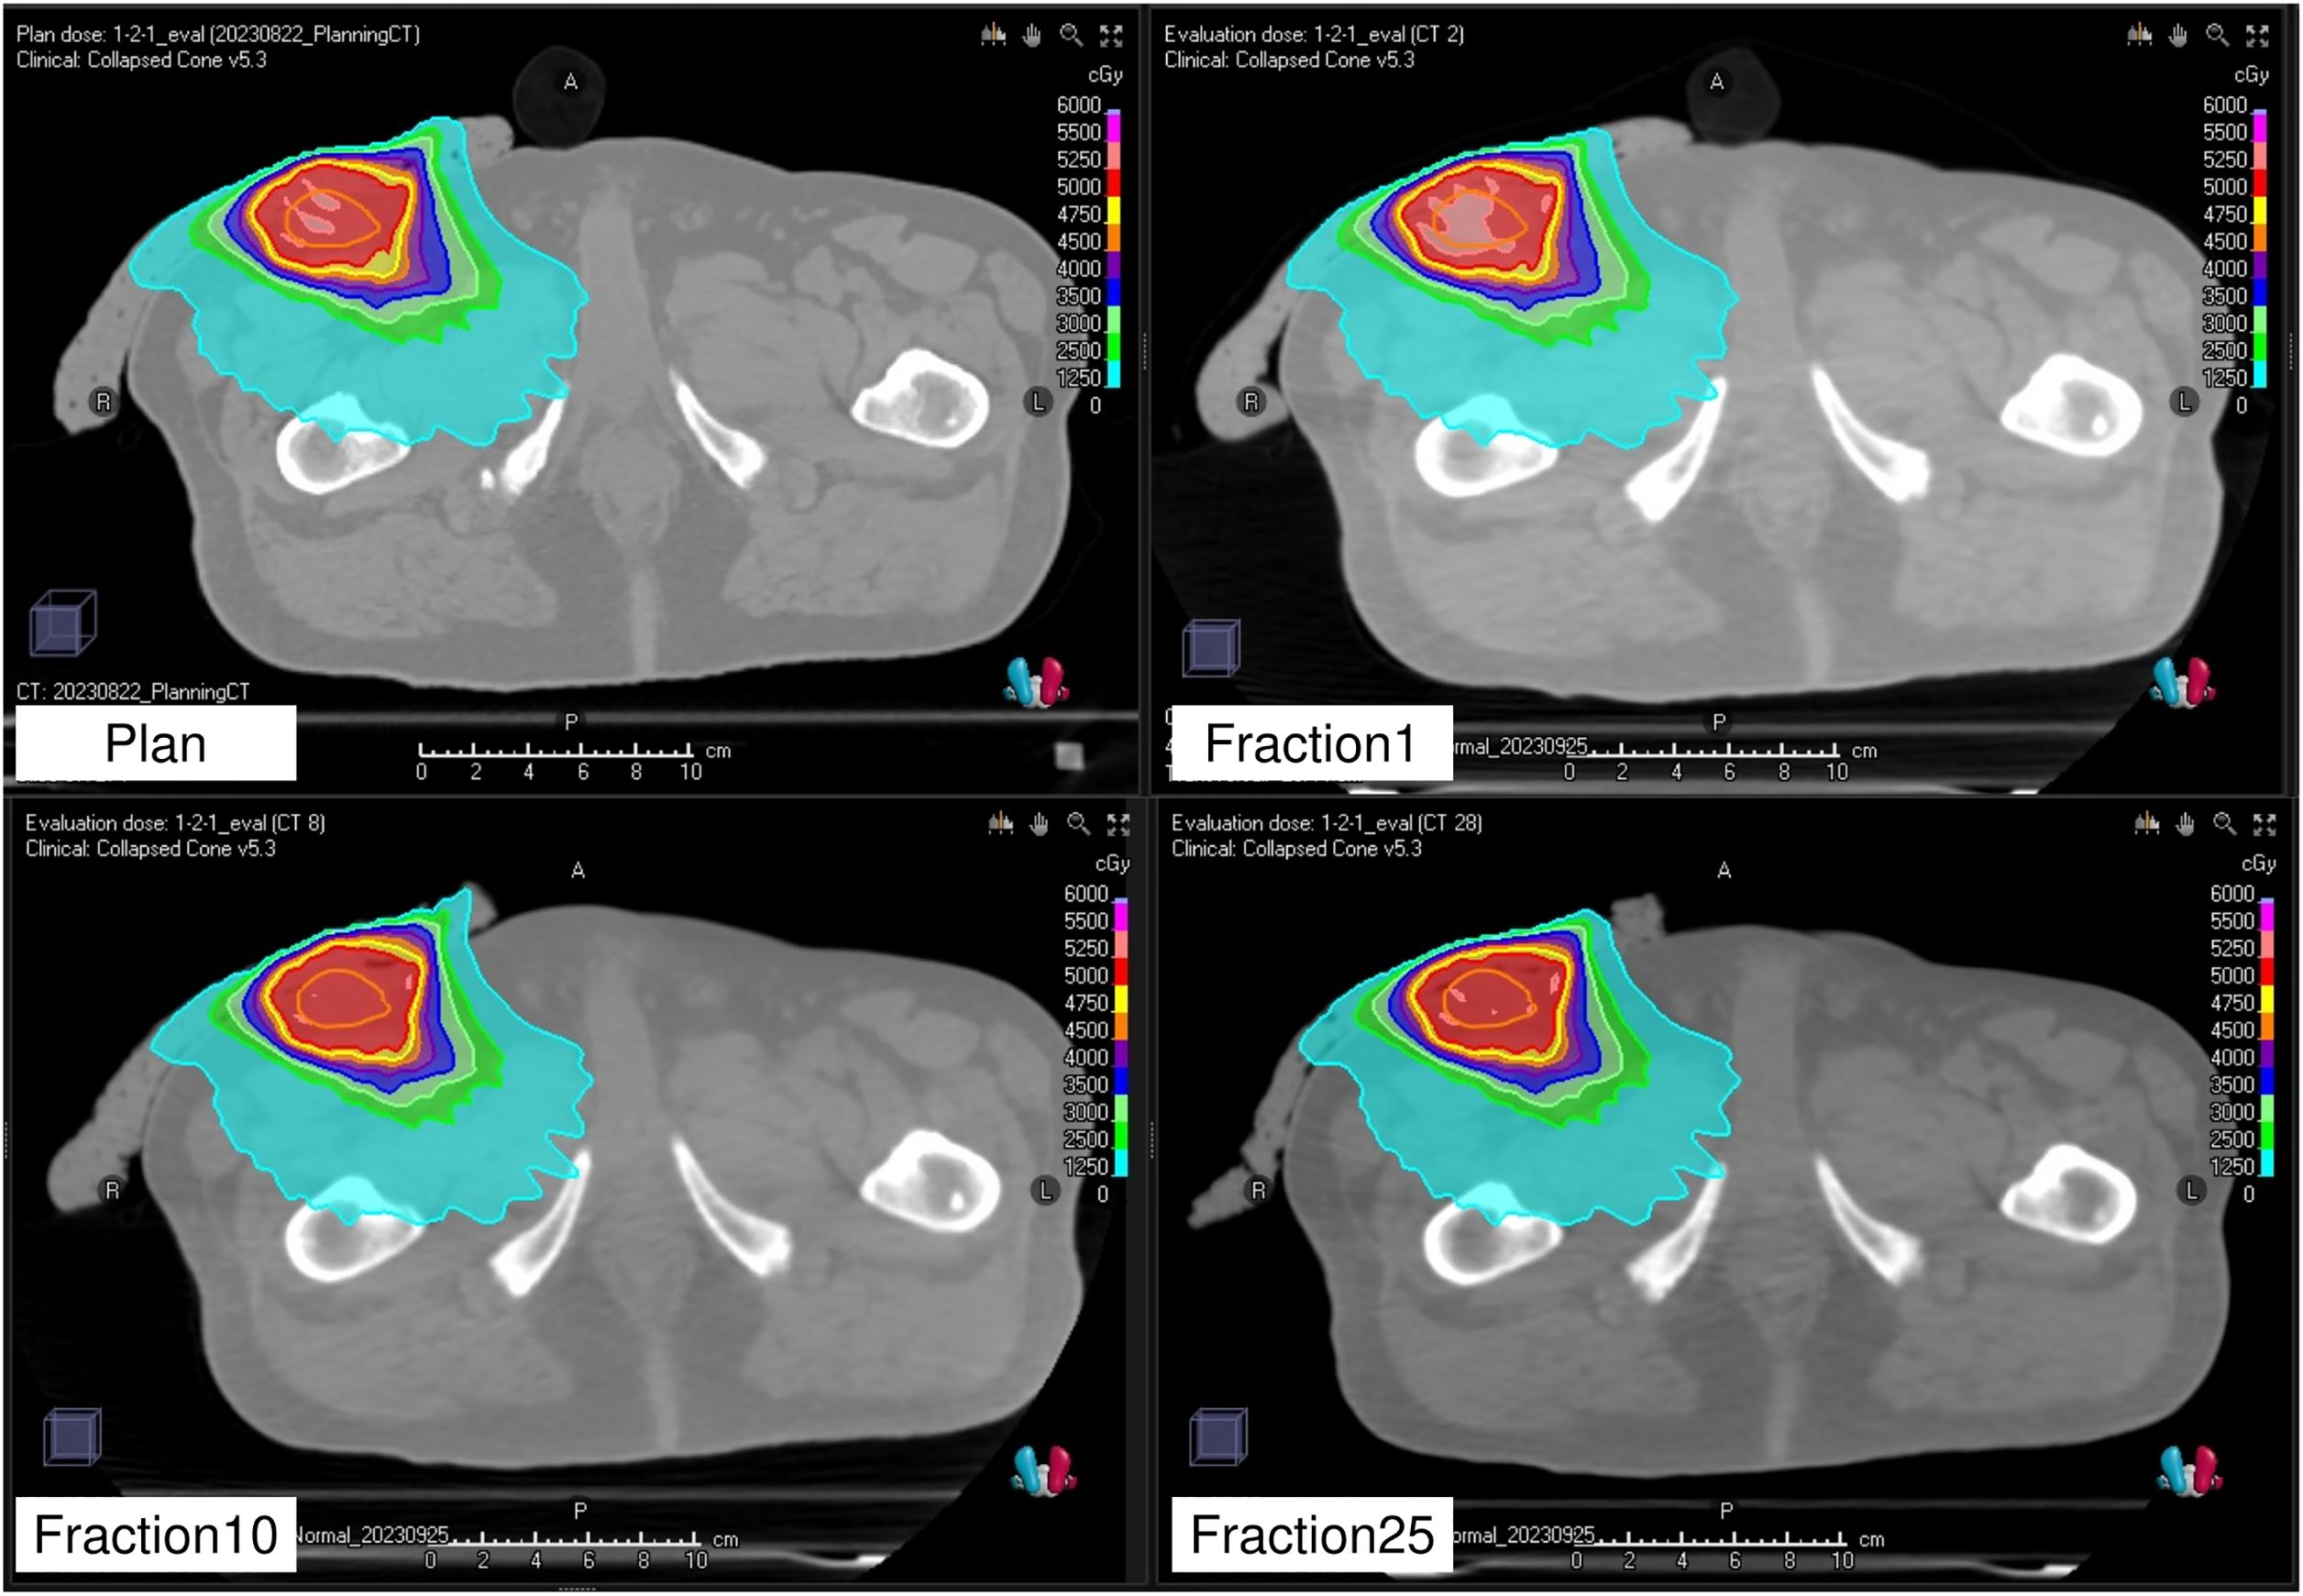

Background: Flat commercial boluses for superficial tumor radiation therapy often fail to conform to irregular body surfaces, resulting in air gaps that reduce dose coverage and uniformity. Although three-dimensional printed custom boluses have been developed to address this issue, the plastic material rigidity and time-consuming fabrication process limit their application. This study aimed to evaluate a flexible and easily moldable Super Stuff bolus as a practical alternative. Methods: We conducted a three-part study using Radixact with the kilovoltage computed tomography (kVCT) system. First, surface dose measurements were performed using radiochromic film on a solid water phantom. Super Stuff boluses of varying thicknesses (up to 20 mm) were compared with commercial boluses. Second, long-term stability was assessed over 65 days for dose delivery, thickness (via CT-based measurements), and CT number. Finally, in a clinical case of Ewing's sarcoma, setup reproducibility and conformity were assessed using Radixact's kVCT imaging. Delivered dose distributions were compared with the planned distribution using dose–volume histogram parameters and gamma analysis. Results: Surface dose measurements demonstrated that the maximum variation in surface dose among Super Stuff boluses with thicknesses ranging from 10.7 to 19.8 mm was within 4%. Over 65 days, the Super Stuff bolus showed good long-term stability. Changes in thickness were limited to a maximum of 1.6 mm, and fluctuations in CT number remained stable at 17.9 ± 1.2 Hounsfield units. In the clinical setting, kVCT imaging provided clear visualization of the Super Stuff bolus, and setup reproducibility was maintained throughout the treatment course. Air gaps were also minimized. Furthermore, gamma analysis (3%/2 mm) confirmed high dosimetric reproducibility throughout the treatment course, with passing rates exceeding 96% between the first and subsequent treatment fractions. Conclusions: The Super Stuff bolus provides notable clinical advantages for treating superficial tumors using Radixact with the kVCT system: consistent surface dose buildup, easy fabrication, and robust long-term physical and dosimetric stability. The seamless integration with the kVCT system enhances setup reproducibility, contributing to reliable and accurate dose delivery throughout the treatment course.